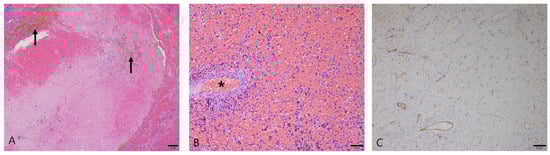

3.2.2. Hematoma

3.2.3. Splenic Hemangiosarcoma